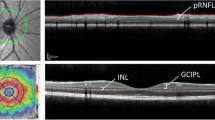

OCT studies in MS have primarily concentrated on conventional OCT measures, namely the average peripapillary RNFL thickness (pRNFL) and average macular thickness (AMT). pRNFL thickness primarily reflects retinal axonal integrity [12], whereas AMT is a non-specific composite measure of all retinal layers. In addition to ganglion cell layer (GCL) and RNFL atrophy, recently described inner and outer nuclear layer pathology in MS may also contribute to AMT reductions [13, 14].

On CAMS and FMS, eight borders were defined (Fig. 1): (1) the inner limiting membrane (ILM); (2) the outer boundary of the macular RNFL (mRNFL); (3) the outer boundary of the inner plexiform layer (IPL); (4) the outer boundary of the inner nuclear layer (INL); (5) the outer boundary of the outer plexiform layer (OPL); (6) the external limiting membrane (ELM); (7) the junction between the inner and outer photoreceptor segments (IS/OS); and (8) Bruch’s membrane (BM). Using these borders, the thicknesses of the following individual and composite layers were defined: 1–2 mRNFL; 2–3 GCL + IPL (GCIP); 3–4 INL; 3–5 INL + OPL; 5–6 outer nuclear layer (ONL); 6–7 inner photoreceptor segments (IS); 5–8 ONL + photoreceptor segments (ONL + PR); and 7–8 retinal pigment epithelium (RPE+).

Cirrus FAS has been described in detail by our group elsewhere [13, 14]. Briefly, segmentation software automatically identifies the ILM, the outer boundaries of the RNFL, IPL, and OPL, and the inner boundary of the RPE, yielding average thickness measurements for (1) mRNFL; (2) GCIP; (3) INL + OPL; and (4) ONL + PR (by this protocol defined as being between the outer boundary of the OPL and the inner boundary of the RPE).